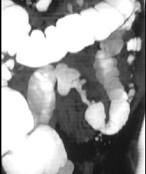

男,55岁,左下腹胀痛、并可触及包块,结合图像,应诊断为()A.结肠Crohn病B.结肠癌C.结肠腺瘤D.肠结核E.慢性溃疡性结肠炎

问题 男,55岁,左下腹胀痛、并可触及包块,结合图像,应诊断为()

选项 A.结肠Crohn病 B.结肠癌 C.结肠腺瘤 D.肠结核 E.慢性溃疡性结肠炎

答案 B